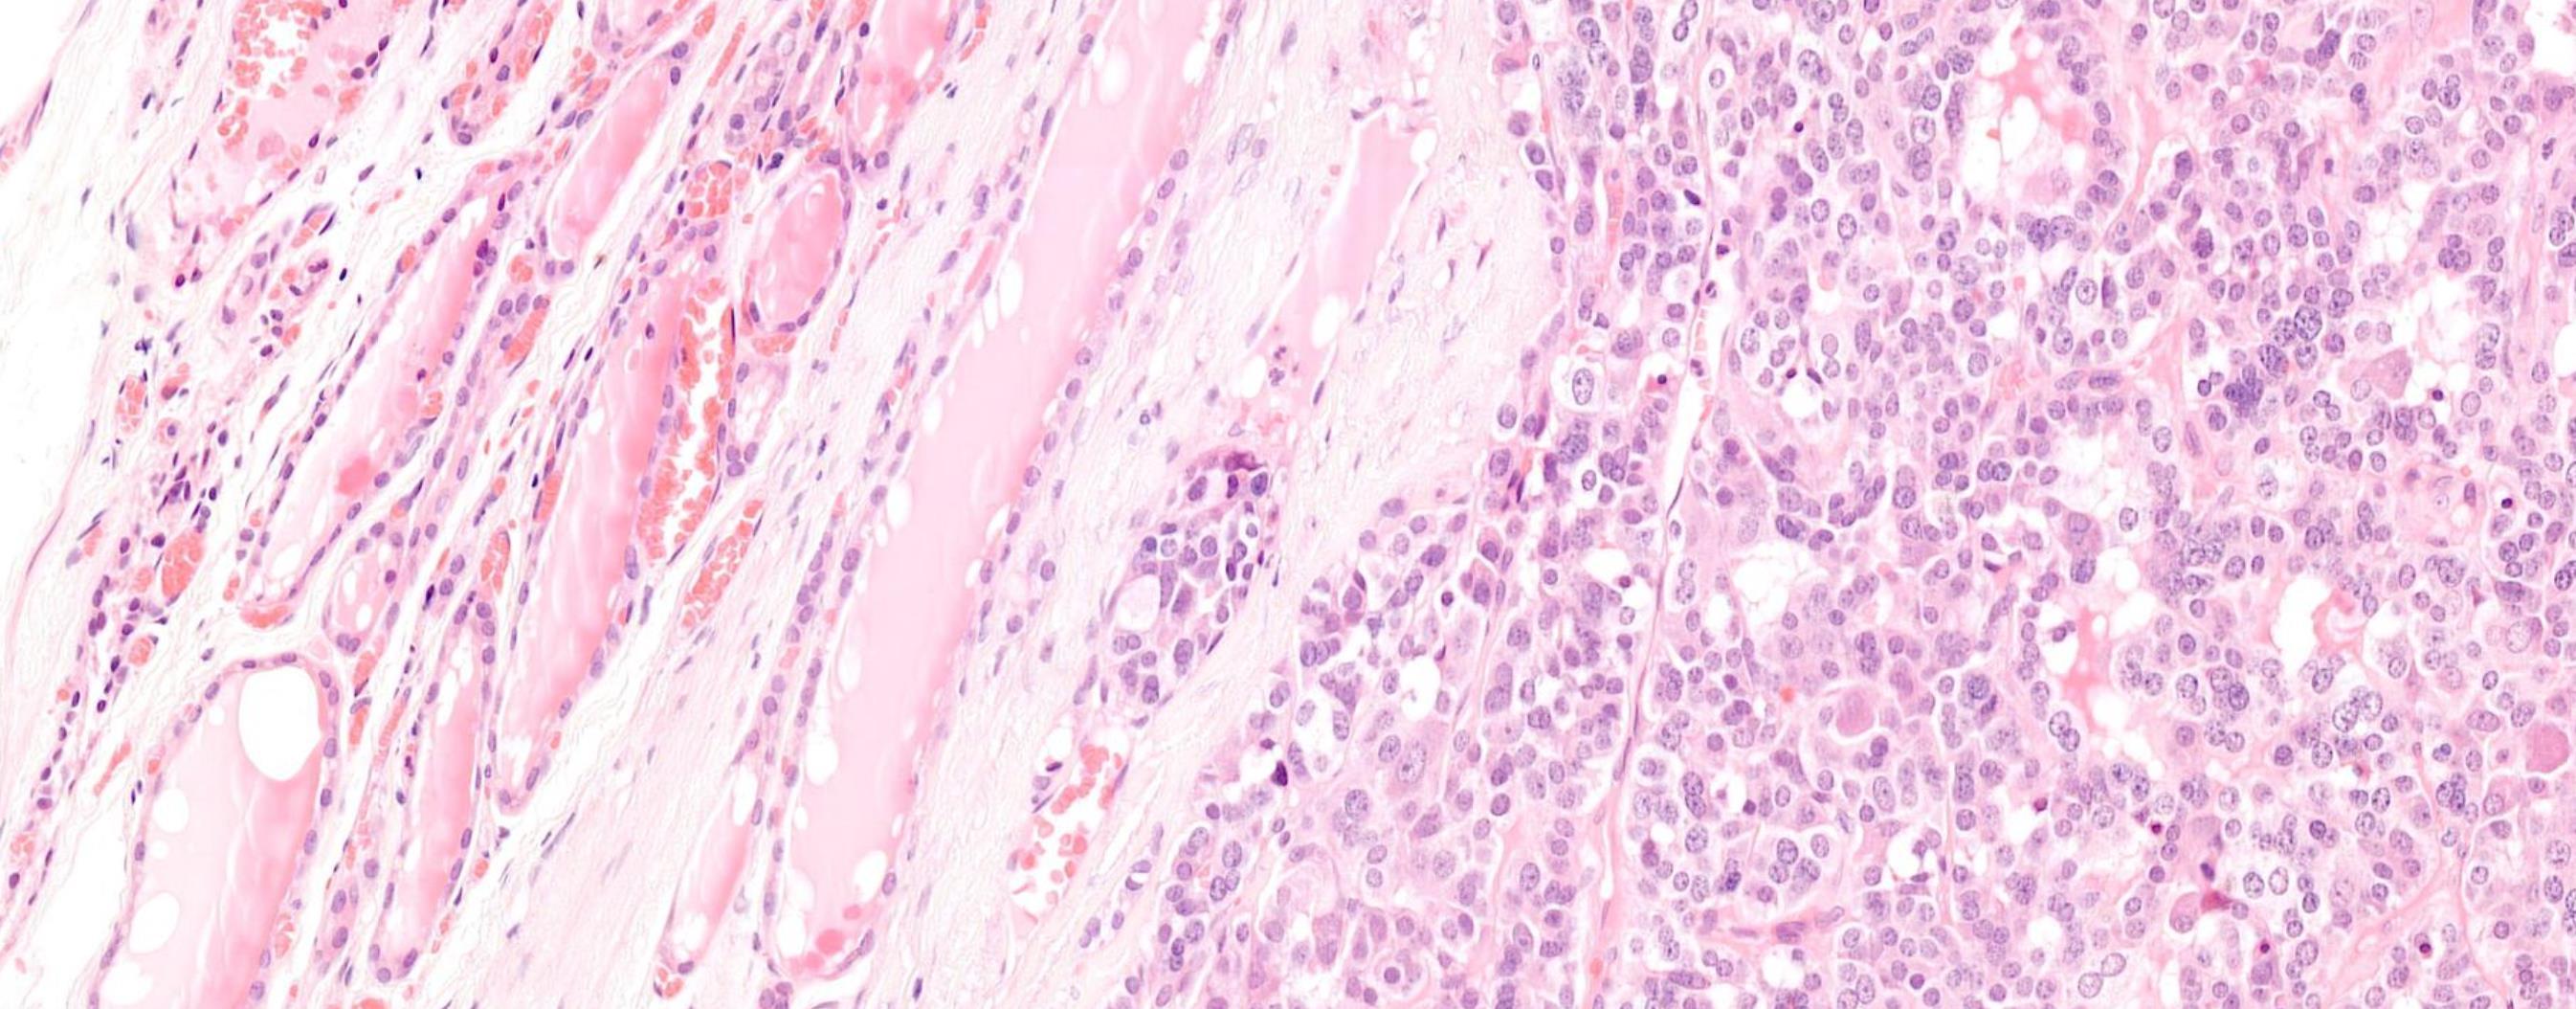

Case 8

Female 51 years Thy 3a left hemithyroid.

Case 8 Diagnosis

Poorly differentiated thyroid carcinoma arising possibly in a columnar cell variant of Papillary thyroid carcinoma

Discussion-Follicular-derived carcinomas, high-grade Subtypes • Poorly differentiated thyroid carcinoma (PDTC)- Insular carcinoma • Differentiated high-grade thyroid carcinoma (DHGTC) Turin consensus criteria for PDTC (i) presence of a solid/trabecular/insular pattern of growth in a tumour diagnosed as malignant based on invasive properties; (ii) absence of conventional nuclear features of papillary carcinoma; (iii) presence of at least one of the following: convoluted nuclei, mitotic count ≥ 3 per 2 mm2 , tumour necrosis DHGTC- ≥ 5 mitosis per 2 mm2 in hot spot + tumour necrosis, at least partially preserved normal tumour histology and immunoprofile

Immunoprofile • Positive for keratins, thyroglobulin, TTF1, and PAX8 • Thyroglobulin expression is typically reduced

• Ki67/MIB-1 usually 10-30%

and focal in poorly differentiated areas often with a peculiar dot-like paranuclear pattern.